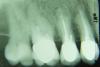

конфьюзд Опубликовано 1 мая, 2007 Поделиться Опубликовано 1 мая, 2007 А это уже стиль работы такой. Одни врачи всегда всё объясняют, другие предпочитают ликбезами не заниматься. Как человек, за время обучения в техническом вузе приученный к тому, что за недостающими знаниями нужно обращаться к литературе, я по этому поводу никогда не печалился Хотя, конечно, при наличии сомнений действительно лучше задавать вопросы сразу... Но все-таки хотелось бы читателям раздела посоветовать, чтобы они не обижались на то, что среди них не провели разъяснительную работу... Дело не в ликбезе, нигде в литературе имхо не написано, что под коронку нужно и соседний зуб пилить (смотрите снимок). До этого тоже было несколько неприятных случаев (перелечили). После этого фобия у меня - боюсь стоматологов хоть тресни - мне нужно все объяснить и успокоить, что не навредят. Я послала email и спросила сколько под вкладку на 17(живой) пилить предется (так как Мартовский сказал, что очень много) - доктор не ответил. Что делать? - не знаю. На снимке 37 под коронкой и 38, который, ничего не сказав, спилили. Как вы думаете, можно ли 37 немного выровнять и отодвинуть от 38 ортодонтическими методами, чтоб они друг другу не мешали, чистить между ними зубной нитью очень трудно, а спиливать до самой десны не хочется. Спасибо всем за ответы Ссылка на комментарий

Мартовский Опубликовано 1 мая, 2007 Поделиться Опубликовано 1 мая, 2007 Дело не в ликбезе, нигде в литературе имхо не написано, что под коронку нужно и соседний зуб пилить (смотрите снимок). До этого тоже было несколько неприятных случаев (перелечили). После этого фобия у меня - боюсь стоматологов хоть тресни - мне нужно все объяснить и успокоить, что не навредят. Я послала email и спросила сколько под вкладку на 17(живой) пилить предется (так как Мартовский сказал, что очень много) - доктор не ответил. Что делать? - не знаю. На снимке 37 под коронкой и 38, который, ничего не сказав, спилили. Как вы думаете, можно ли 37 немного выровнять и отодвинуть от 38 ортодонтическими методами, чтоб они друг другу не мешали, чистить между ними зубной нитью очень трудно, а спиливать до самой десны не хочется. Спасибо всем за ответы Может он просто почту раз в неделю смотрит, вот и не ответил. Если,как вы говорите, врач хороший, то он вам так вкладку поставит, что вы про нее забудете лет на 10 - 15. А то что плохой церек или хороший, целесообразно так много пилить или нет - это больше наши с коллегами разногласия - мы будем спорить до хрипоты и навряд ли придем к чему либо одному. Выровнять и отодвинуть конечно можно, только я бы не стал. Наверное дешевле снять эту корнку, полечить 38 и поставить коронку новую. Не только по деньгам дешевле, но и для вас проблем меньше будет Ссылка на комментарий